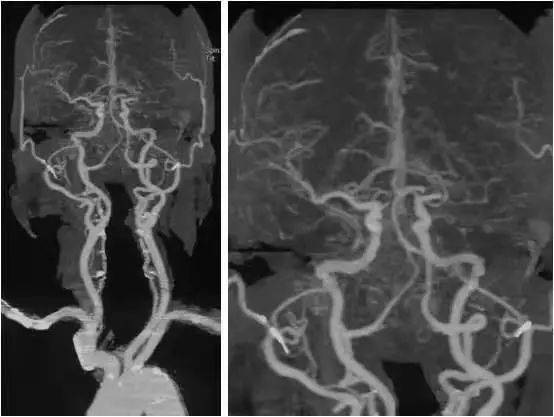

MS的 MRI特點(diǎn)。

側(cè)腦室周圍、半卵圓中心、胼胝體與腦室間可見(jiàn)類圓形或融合性斑塊, T1W I低信號(hào) 、T2WI高信號(hào),大小不一,常見(jiàn)于側(cè)腦室前角和后角周圍,大融合性斑塊多累及側(cè)腦室體部, 腦干、小腦、脊髓可見(jiàn)不規(guī)則斑塊。 MS患者病程較長(zhǎng)可伴腦室系統(tǒng)擴(kuò)張、腦溝增寬等腦白質(zhì)萎縮征象。

T2W I顯示大腦白質(zhì)MS斑塊較好, 質(zhì)子密度加權(quán)像顯示腦干和小腦斑塊較清晰,T1W I可鑒別MS陳舊與新鮮斑塊,前 者 T1W I呈明顯低信號(hào),注 射 Gd-DTPA后不強(qiáng)化,后者呈模糊等信號(hào),有顯著強(qiáng)化效應(yīng)。 MRI診斷顱內(nèi)多發(fā)性脫髓鞘病變注意事項(xiàng)。

MRI在臨床的廣泛應(yīng)用發(fā)現(xiàn)許多顱內(nèi)多發(fā)性病變, 腫瘤、腦梗死、寄生蟲(chóng)病等常可確診, 許多原因不明的顱內(nèi)多發(fā)性病變往往根據(jù)其形態(tài)及分布范圍被歸為“脫髓鞘”病變,導(dǎo)致對(duì)脫髓鞘及脫髓鞘疾病概念認(rèn)識(shí)的混亂。 腦室旁T2W I高信號(hào)可見(jiàn)于多種病理過(guò)程,甚至正常的老年人,但老年人改變常較輕微, T2W I顯示數(shù)個(gè)不對(duì)稱的界限清楚、緊鄰腦室表面病灶常提示MS, 與纖維束走行一致的放射性分布的脫髓鞘區(qū)更有診斷意義,急性期病灶有增強(qiáng)效應(yīng)。

顱內(nèi)多發(fā)性脫髓鞘病變典型地見(jiàn)于多發(fā)性硬化患者, CNS脫髓鞘病變是自身免疫機(jī)制導(dǎo)致。然而,多種神經(jīng)系統(tǒng)病變?nèi)缪h(huán)障礙、中毒、感染、變性及營(yíng)養(yǎng)障礙等均可導(dǎo)致脫髓鞘或類似脫髓鞘病變,是廣義的脫髓鞘疾病,后者應(yīng)根據(jù)患者的臨床表現(xiàn)、自然病程、病變影像學(xué)特點(diǎn)及治療反應(yīng)等與MS鑒別,避 免 CNS脫髓鞘病變的臨床誤診或過(guò)度診斷。